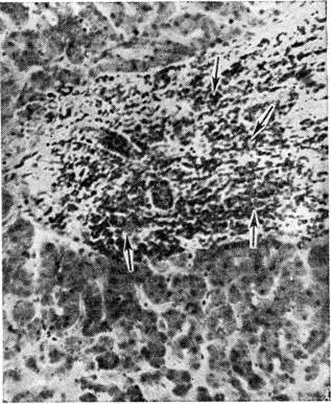

В костном мозге, по данным трепанобиопсии, на первых стадиях заболевания скопления бластных клеток являются очаговыми, в достаточном количестве обнаруживаются элементы деятельного костного мозга. Нередко наблюдаются острые расстройства кровообращения, участки гипоплазии, могут обнаруживаться некрозы. Прогрессирование заболевания характеризуется увеличением числа и размеров лейкозных разрастаний, их слиянием, а затем диффузной инфильтрацией ткани костного мозга. Количество нормальных кроветворных клеток заметно уменьшается. Часто имеется инфильтрация надкостницы, возможно распространение процесса в окружающие мягкие ткани. Развитие лейкозных разрастаний сопровождается выраженным рассасыванием костной ткани, преимущественно по типу гладкой резорбции. Очень редко в этом процессе принимают участие остеокласты. Вследствие частичного, а местами и полного рассасывания костных балок происходит значительное расширение костномозговых полостей, истончение, а в некоторых участках разрушение кортикального слоя. В раннем детском возрасте резкие изменения наблюдаются в зоне энхондрального окостенения. При острых Лейкозы редко отмечается очаговое новообразование атипичной костной ткани, богатой остеоидом, разрастание фиброзной ткани. Наряду с мелкими фокусами некроза иногда возникают обширные инфарктообразные коагуляционные некрозы, определяемые макроскопически в виде жёлто-белых сухих участков; в окружности наблюдаются кровоизлияния, возможно скопление макрофагов (рисунок 1). В области лейкозных разрастаний нередко обнаруживается истончение и частичный распад ретикулярных волокон. Описаны наблюдения с очаговым или диффузным миелофиброзом, который чаще выявляется при миелобластном Лейкозы. В таких случаях при пункции обычно не удаётся получить костный мозг и для установления диагноза необходимо исследование материала трепанобиопсии.

Лейкозная инфильтрация ткани селезёнки и лимфатических, узлов сопровождается уменьшением размеров (рисунок 2) и числа фолликулов вплоть до полного их исчезновения. В селезёнке часто наблюдается инфильтрация трабекул с разволокнением стенок трабекулярных сосудов, с деформацией и сужением их просвета, имеются поля кровоизлияний. В лимфатических, узлах вначале возникают очаговые инфильтраты, которые по мере прогрессирования болезни увеличиваются в размерах, и поражение становится диффузным.

При всех формах Лейкозы наиболее интенсивное подавление лейкозной инфильтрации наблюдается в костном мозге. При вскрытии костный мозг плоских костей очагово или на всем протяжении суховатый, серого или серо-жёлтого цвета, в нем имеются участки жировой ткани и тёмно-красные поля кровоизлияний. При микроскопическом исследовании количество клеток в костном мозге снижено, видны поля опустошения различной величины, состоящие из отёчной стромы с наличием макрофагов и единичных бластных клеток (рисунок 8), зоны геморрагического пропитывания. Лейкозные инфильтраты располагаются очагово, содержат много клеток в состоянии лизиса, пикноза, распада (рисунок 9). Могут встречаться очаги некроза, представленные распадающимися лейкозными клетками, а также участки тотального коагуляционного некроза ткани с одновременной гибелью стромы. Иногда видны гигантские клетки с уродливыми гиперхромными ядрами, появление которых связывают с дистрофическими изменениями бластных элементов. Такие же клетки иногда выявляются в других органах.